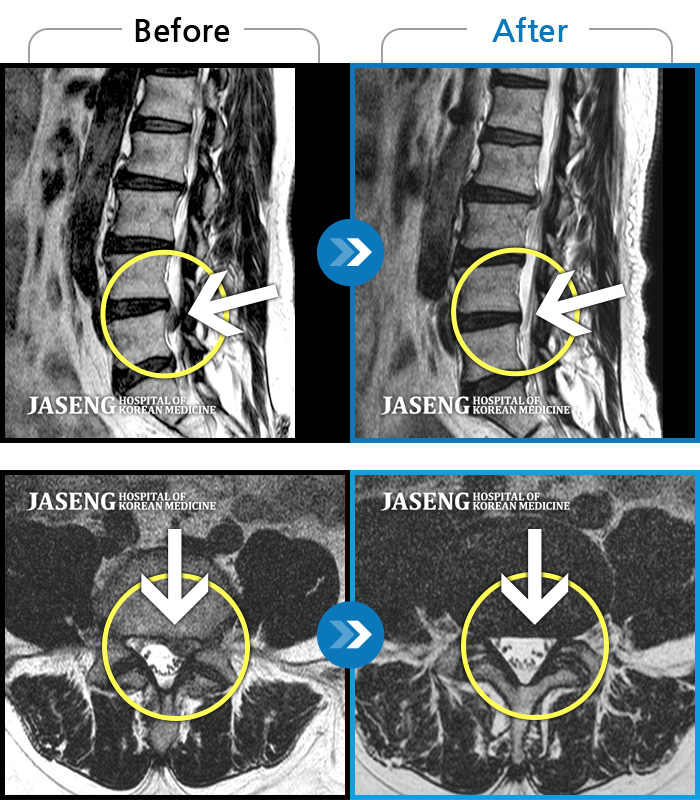

Before

After

환자에게 사전 동의를 받아 동일 조건에서 촬영되었습니다.

개인에 따라 치료 후 부작용이 발생할 수 있으니 의료진과 상담 후 치료를 진행하시기 바랍니다.

하지 저림과 통증이 개선되어서 일상생활이 너무 즐겁습니다.

처음 내원 시 허리와 다리 통증이 심한 상태로 내원하셨습니다.